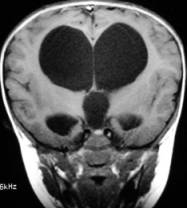

脑积水的预防及措施

脑积水儿的产前早期诊断是预防脑积水儿出生的重要途径。由于明显的脑积水,在孕12——18周即可通过B超查出,所以要加强B超在产前诊断中的应用,及早终止妊娠,预防脑积水儿的出生,降低先天性脑积水的出生率。